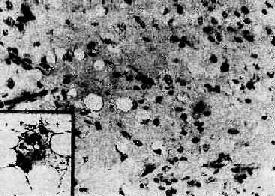

3.脂肪内(liposarcoma) 为肉中较常见的一种类型,多发生于大腿及腹膜后的软组织深部。来自原始间叶组织,极少从皮下脂肪层发生,与脂肪的分布相反。这说明脂肪肉极少是由脂肪恶变而来,而是一开始即具恶性特征。本多见于40岁以上成人,极少见于青少年。肉眼观,大多数肿呈结节状或分叶状,表面常有一层假包膜,可似一般的脂肪,亦可呈粘液性外观,或均匀一致呈鱼肉样。本细胞形态多种多样,可见分化差的星形、梭形、小圆形或呈明显异型性和多形性的脂肪母细胞,胞浆内可见多少和大小不等的脂滴空泡(图7-18),也可见分化成熟的脂肪细胞,并常以某种细胞成分为主。间质有明显粘液性和大量血管网形成者,称为粘液样型脂肪肉。当以分化差的小圆形脂肪母细胞为主(圆形细胞型脂肪肉)或以多形性脂肪母细胞为主时(多形性脂肪肉),恶性程度高,易有复发和转移。

图7-18 脂肪肉

细胞分散,胞浆内含大小不等的脂肪空泡。细胞间有多量粘液性基质(图中呈灰色),并见巨细胞(插入图)